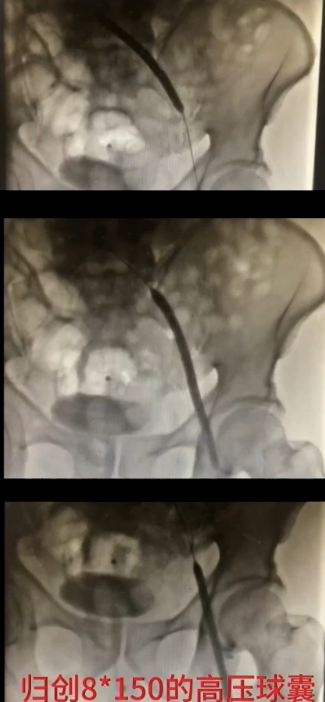

手术过程(四):退出抽吸导管后,复查造影,股浅静脉内血栓消失,但血流速度仍缓慢,提示近心端仍有梗阻。使用高压球囊扩张髂静脉,可见髂总静脉明显狭窄。分段扩张完成后,引入12 mm×40 mm球囊继续扩张。